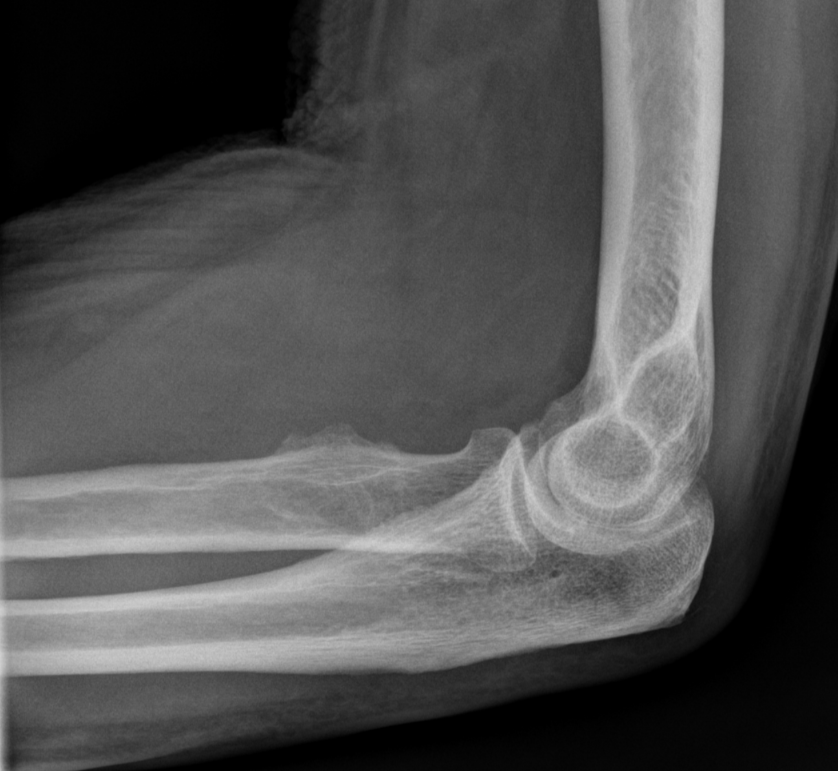

3. Radial tuberosity enthesitis (distal biceps)